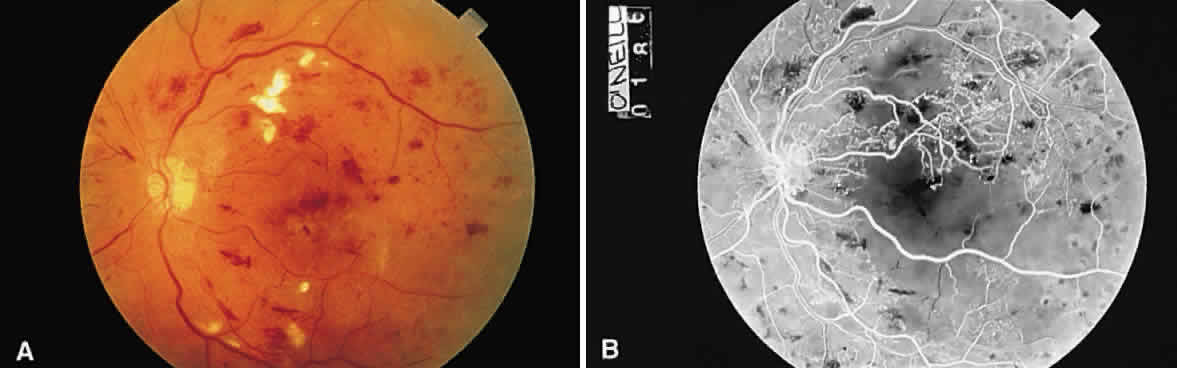

Fig. 13. A. Fundus photograph of a subpigment epithelium hemorrhage superotemporal

to the disc secondary to a macroaneurysm. Notice its dark color and sharp

border. The central portion of the hemorrhage has extended through

the sensory retinal to the subinternal limiting membrane area. B. Fluorescein angiography showing the retinal vessels overlying the deep

hemorrhage but obscured by the central extension anteriorly. (B, courtesy of William Tasman, MD, Philadelphia, PA) Fig. 13. A. Fundus photograph of a subpigment epithelium hemorrhage superotemporal

to the disc secondary to a macroaneurysm. Notice its dark color and sharp

border. The central portion of the hemorrhage has extended through

the sensory retinal to the subinternal limiting membrane area. B. Fluorescein angiography showing the retinal vessels overlying the deep

hemorrhage but obscured by the central extension anteriorly. (B, courtesy of William Tasman, MD, Philadelphia, PA)

|